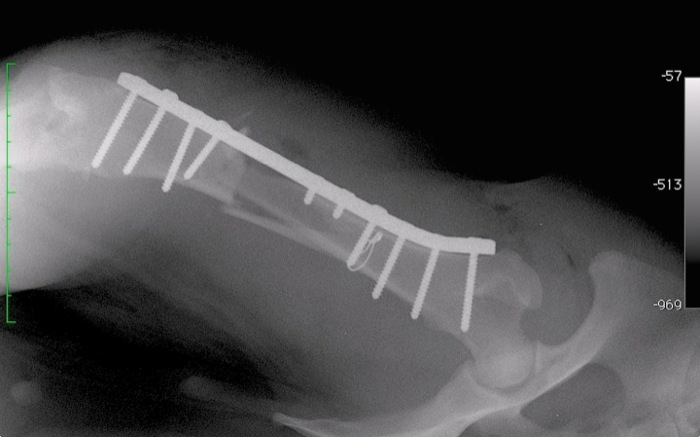

| Tratamiento | Se coloca una placa que en este caso es de 4 mm de grosor dada la fractura y el peso del animal. Previamente se fija, con alambre de 0,8 mm, el único gran fragmento musculado que impedirá complicaciones por necrosis y facilitará su osificiación. El resto aparecen totalmente sueltos y se retiran sobre todo por tratarse de fractura abierta y llevar 3 días. |

Se opta por una placa de 4 mm de grosor que de la máxima resistencia. En alguna ocasión este material que parece irrompible se parte incluso en animales de talla reducida.

El resultado es 100% estable con 8 tornillos firmes a sus 16 corticales y otros 2 tornillos que se fijan sólo a la cortical proximal. Algunos tornillos no son perpendiculares a la placa para fijarse también a la cortical distal allí donde se han perdido esquirlas.